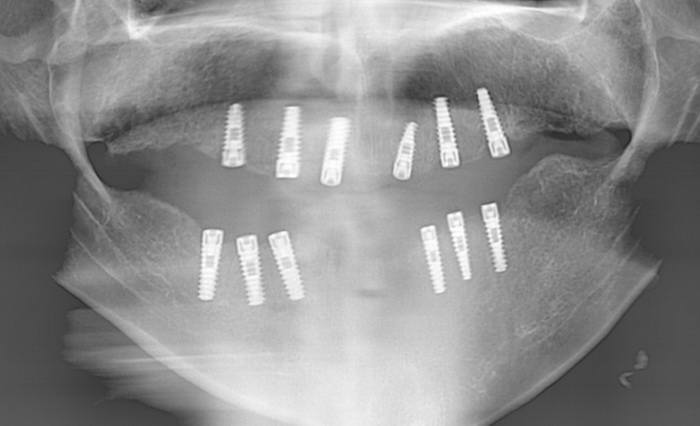

| لمشاهدة بعض الحالات التي تم زراعتها في مركز أسنانك الدولي بإمكانكم مشاهدة هذا الفيلم الصغير مع شرح مبسط |

| حالة زراعة أسنان صعبة |